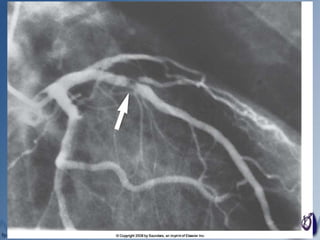

 Coronarografia

 Ecografia intravasculară ( IVUS)

Artera stângă descendentă anterioară (LAD)

 este ramura principală a arterei

coronare stângi

 irigă:

 cea mai mare parte a feţei ant. a VS

 versantul anterior al feţei laterale

 vârful inimii

 o mică fâşie din peretele anterior al VD

 2/3 anterioare şi apicale ale SIV (sept interventricular)

 infarctele în teritoriul acestei artere sunt denumite

anterioare, antero-septale şi antero-laterale